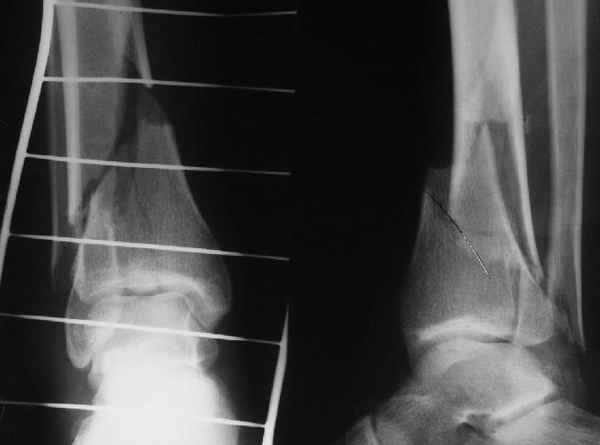

АЧ>Какие тут аргументы в пользу выбора пластины, а не интрамедуллярного гвоздя?

Классически показанием для locked nail яв-ся зоны BC CD, до появления LCP показания к locked nail несколько расширялись в зоны AB и DE

Аргументы: перелом достаточно низкий, трудно будет ввести 3-и блок. винта, а учитывая характер перелома на 2-х дистальных винтах я бы не рекомендовал немедленную полную нагрузку.

С Уважением А.Миронов

Кликните для загрузки файла DSC00841.JPG

42KB (43152 bytes)

АМ> Классическим показанием для locked nail яв-ся зоны BC CD, до появления

АМ> LCP показания к locked nail несколько расширялись в зоны AB и DE

Ну, эти "классические" показания были актуальны в соответствующий период, на сегодня их можно пересмотреть. Безотносительно к появлению других фиксаторов, гвоздиками можно фиксировать переломы если не дистальнее линии E или проксимальнее A, то уж практически на их уровне.

Если недоступны гвозди, специально разработанные для очень дистальных переломов, то всегда под рукой возможность спилить лишнее, чтобы отверстие оказалось на самом кончике.

АМ> Аргументы: перелом достаточно низкий, трудно будет ввести 3-и блок.

АМ> винта, а учитывая характер перелома на 2-х дистальных винтах я бы не

АМ> рекомендовал немедленную полную нагрузку.

Положим, и с 2 винтами она к 2 месяцам была бы тут вполне реальна. Кроме того, есть возможность ввести винты мимо гвоздя (Poller), и таки разрешить раннюю полную нагрузку (что еще зависит от массы тела пациента и диаметра винтов). А уж если сопоставить стоимость отечественного гвоздика и пластины Synthes... Если бы на порядок более дорогая железка давала на тот же порядок лучший результат... ;-)